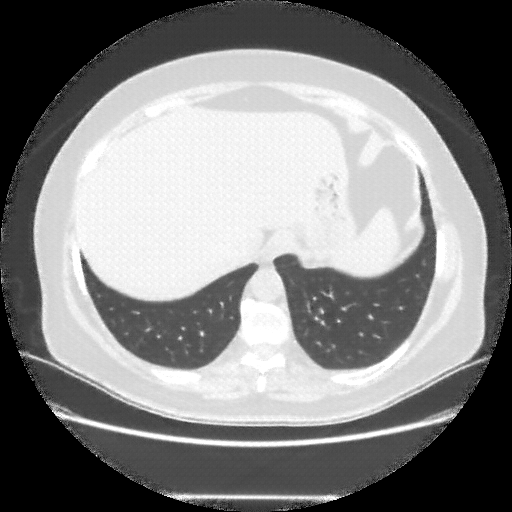

Original NATIVE CT scan (input)

Full window (WL 1023.5, WW 4095 β†’ Low βˆ’1024, High +3071)

Actual HU range: [-1024.0, 918.0]